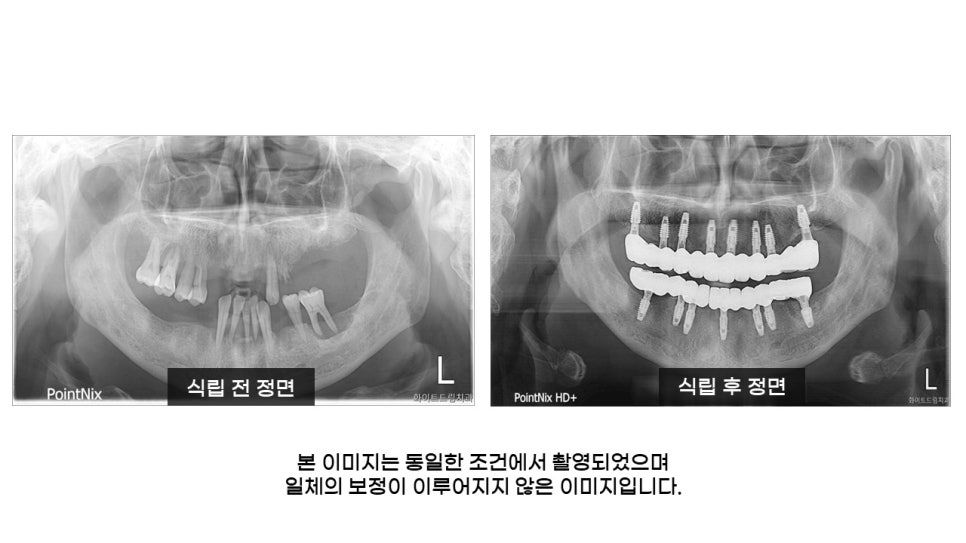

환자분의 식립 전 사진을 살펴보면 치주염이 진행되고 있었고 상악 앞니와 어금니, 하악 어금니 부분이 탈락되어 있었으며, 치열도 고르지 못하셨는데요.

치아가 빠지고 난 후 오랜시간이 지나다 보니 치아가 한쪽으로 쏠리면서 치열이 무너졌으며, 교합관계에 있는 치아도 불규칙하게 이동해 있었습니다.

전체치아 발치라는게 환자의 입장에서 부담스러울 수 있지만, 현재 치아를 유지한다면 나머지를 임플란트 식립을 한다 하여도 현재 겪는 불편함을 해소하기에는 어렵기 때문에 상악 8개, 하악 7개 식립 후 12개의 치아를 완성하여 저작기능 및 심미성을 회복시켜드릴 수 있도록 도와드렸습니다.

이어서 쉽게 확인해보실 수 있도록 준비한 식립 전 전체 파노라마입니다.

파노라마 상으로 치조골이 흡수되어 전체적으로 잇몸뼈가 많이 무너져 내린 상태 이신 것을 확인 할 수 있었는데요.

보여드리는 사진은 전체임플란트식립 후의 모습입니다.

상악과 하악 임플란트 모두 각도와 간격이 적절하게 식립됐으며, 신경을 건드리지 않도록 면밀하게 진행해드렸는데요.

한눈에 봐도 임플란트 전후 상태가 확연한 차이가 드러나죠? 치아가 없어서 나이에 비해 노안으로 보일 수 있는 점까지 개선되었습니다.